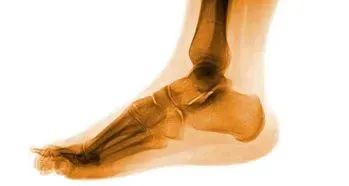

踝关节骨折在临床上非常常见,当踝关节内、外损伤时,往往造成内、外踝和后踝的骨折,可以是单踝骨折、双踝骨折或三踝骨折,出现踝关节的肿胀、疼痛及活动受限。